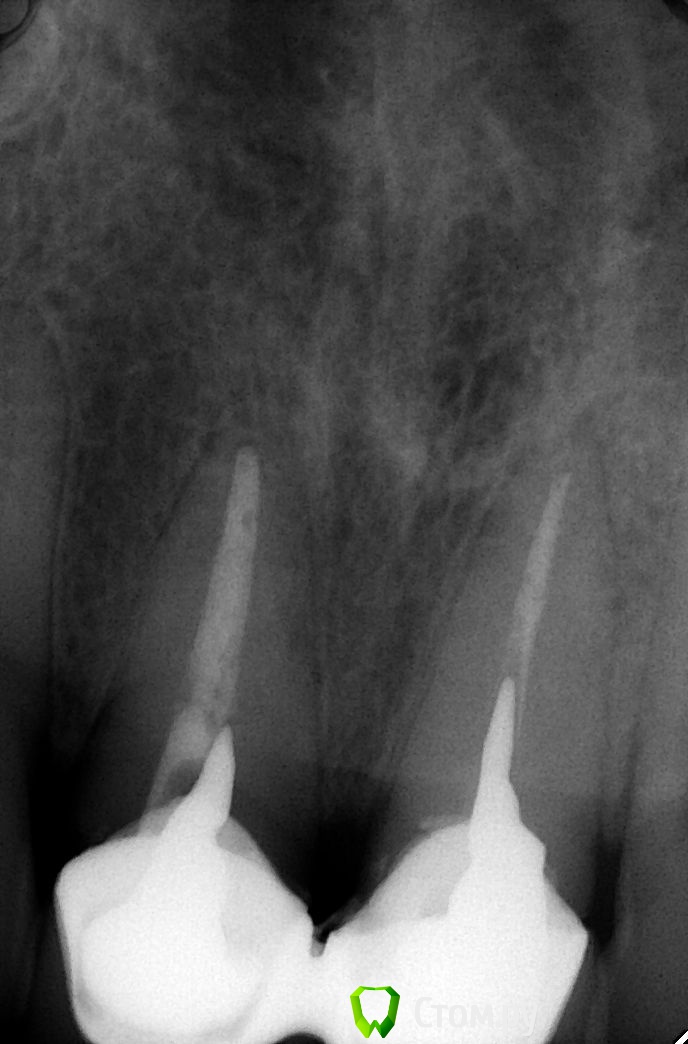

DmitrySH Опубликовано 6 декабря, 2013 Поделиться Опубликовано 6 декабря, 2013 Нужно всю работу переделать. Вкладки слишком короткие 2 Ссылка на комментарий

alexjuk1 Опубликовано 12 декабря, 2013 Автор Поделиться Опубликовано 12 декабря, 2013 Не те снимки загрузились. При попытке извлечь вкладку, корень зуба сломался, врач, при осмотре, еще раньше сказал, что зуб сломан, т.к. десна мягкая и там гной и кровь. На оставшийся корень будут ставить новую вкладку, а что делать со сломанным? Можно ли на этот остаток поставить вкладку или - только удаление? Зуб жалко... Если удалять и ставить имплант - возможно ли одновременно удалить зуб и установить имплант? И как быть с эстетикой, если на установку импланта потребуется полгода? 1 Ссылка на комментарий

alexjuk1 Опубликовано 12 декабря, 2013 Автор Поделиться Опубликовано 12 декабря, 2013 Это после удаленя вкладок http://s017.radikal.ru/i409/1312/0d/08f66403fab8.jpg http://s018.radikal.ru/i504/1312/fc/8f7b62fdc344.jpg Ссылка на комментарий

alexjuk1 Опубликовано 12 декабря, 2013 Автор Поделиться Опубликовано 12 декабря, 2013 Это до удаленя вкладок http://s019.radikal.ru/i608/1312/90/fbe949093d63.jpg http://s020.radikal.ru/i723/1312/46/18e6f5db6dea.jpg Ссылка на комментарий